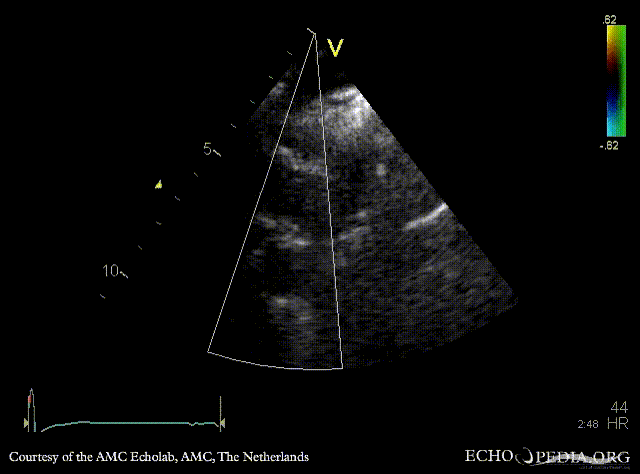

| Suprasternal view | Suprasternal view with Color Doppler |